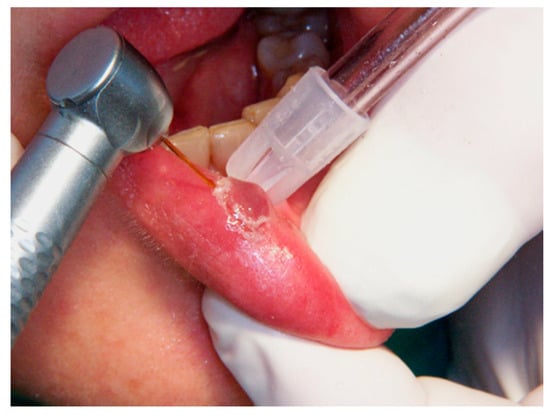

2.3.1. Er,Cr:YSGG Laser

2.3.4. Diode Laser